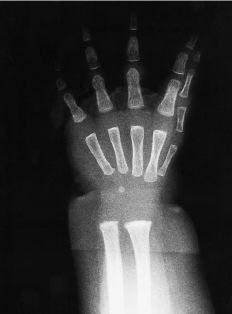

Figura 1. Caso 1. A: Mano derecha con siete dedos. B: Imagen radiográfica de ambas manos; el radio central es algo más grueso y parece el eje de la mano. C: Ambos pies con los cuatro dedos externos normales y aspecto global de pies en espejo.

Revisando la literatura no se encuentra ningún caso descrito con todas las características del caso 1, que presenta claramente unas manos y unos pies en espejo: la duplicación se manifiesta en relación a un eje localizado en el dedo central, que es más grueso, que parecía común a dos manos incompletas, una a cada lado, pero sin la amplia comisura típica de la mano en espejo, y esto en ambas manos y pies. Quizá la presencia de cúbito y radio y no de dos cúbitos como en el caso 5 explicaría la unión de las dos manos y no su separación, que en cierta manera mostraría la parte cubital de cada mano articulada a su respectivo cúbito. Sin embargo, en el caso descrito por King y cols.,8 que es unilateral y no afecta los pies, había cúbito y radio y los dos grupos de dedos estaban separados por una gran comisura, que es mucho menor en el caso de Yang y cols.,14 también unilateral y sin afectación de los pies. La hipoplasia de tibias que presenta este caso 1 se describe también en el caso publicado por Martín y cols.,11 pero en él los dedos tanto de manos como de pies están todos en sindactilia.